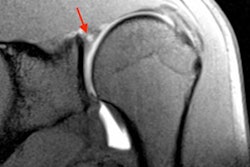

The researchers focused specifically on ultrasound assessment of the rectus femoris and anterior tibialis muscles in young patients (median age, 40). The patients were tube fed as soon as they were stable and fully resuscitated, usually within 24 hours, the group wrote; some patients received a standard feeding formula, while others received a high-protein formula. Patients underwent ultrasound evaluation within 24 hours of the trauma event (day 0) and again at five days, 10 days, 15 days, and 20 days.

To measure muscle changes, the researchers tracked the anterior-posterior and lateral-lateral diameters of the muscles, as well as their cross-sectional area, which is calculated from the perimetral contour of the muscle area and is considered to be proportional to the total mass of the skeletal muscle.